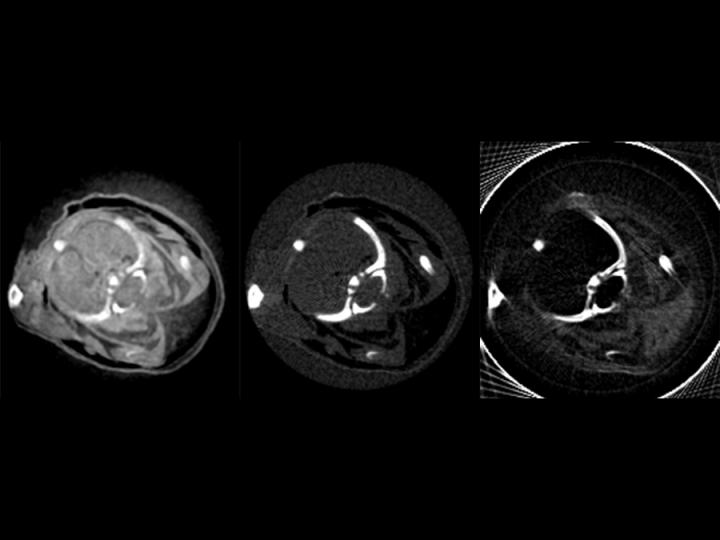

Soft tissue disorders like tumors are very difficult to recognize using normal X-ray machines. There is hardly any distinction between healthy tissue and tumors. Researchers at the Technische Universität München (TUM) have now developed a technology using a compact synchrotron source that measures not only X-ray absorption, but also phase shifts and scattering. Tissue that is hardly recognizable using traditional X-ray machines is now visible.

The scientists inserted an optical grating into the focused X-ray beam, allowing them to detect even tiniest phase shifts and scattering of the radiation in addition to the absorption of X-rays. The first phase contrast tomography image from a compact synchrotron source was successfully acquired.

The phase contrast, dark field and absorption images made using the new technology have complementary properties. Liquid in tissue that remains indiscernible and, thus, invisible using conventional X-ray tubes, suddenly comes to life. The greatly improved soft tissue contrast of the new X-ray technology could also help make tumors detectable earlier on and enable quick diagnoses - in medical emergencies, for example.

The clarity of the new technology becomes apparent when comparing white and brown fatty tissue. "In a mouse we were able to recognize not only heart, liver and other organs much better, but could even differentiate between brown and white body fat," says Eggl.